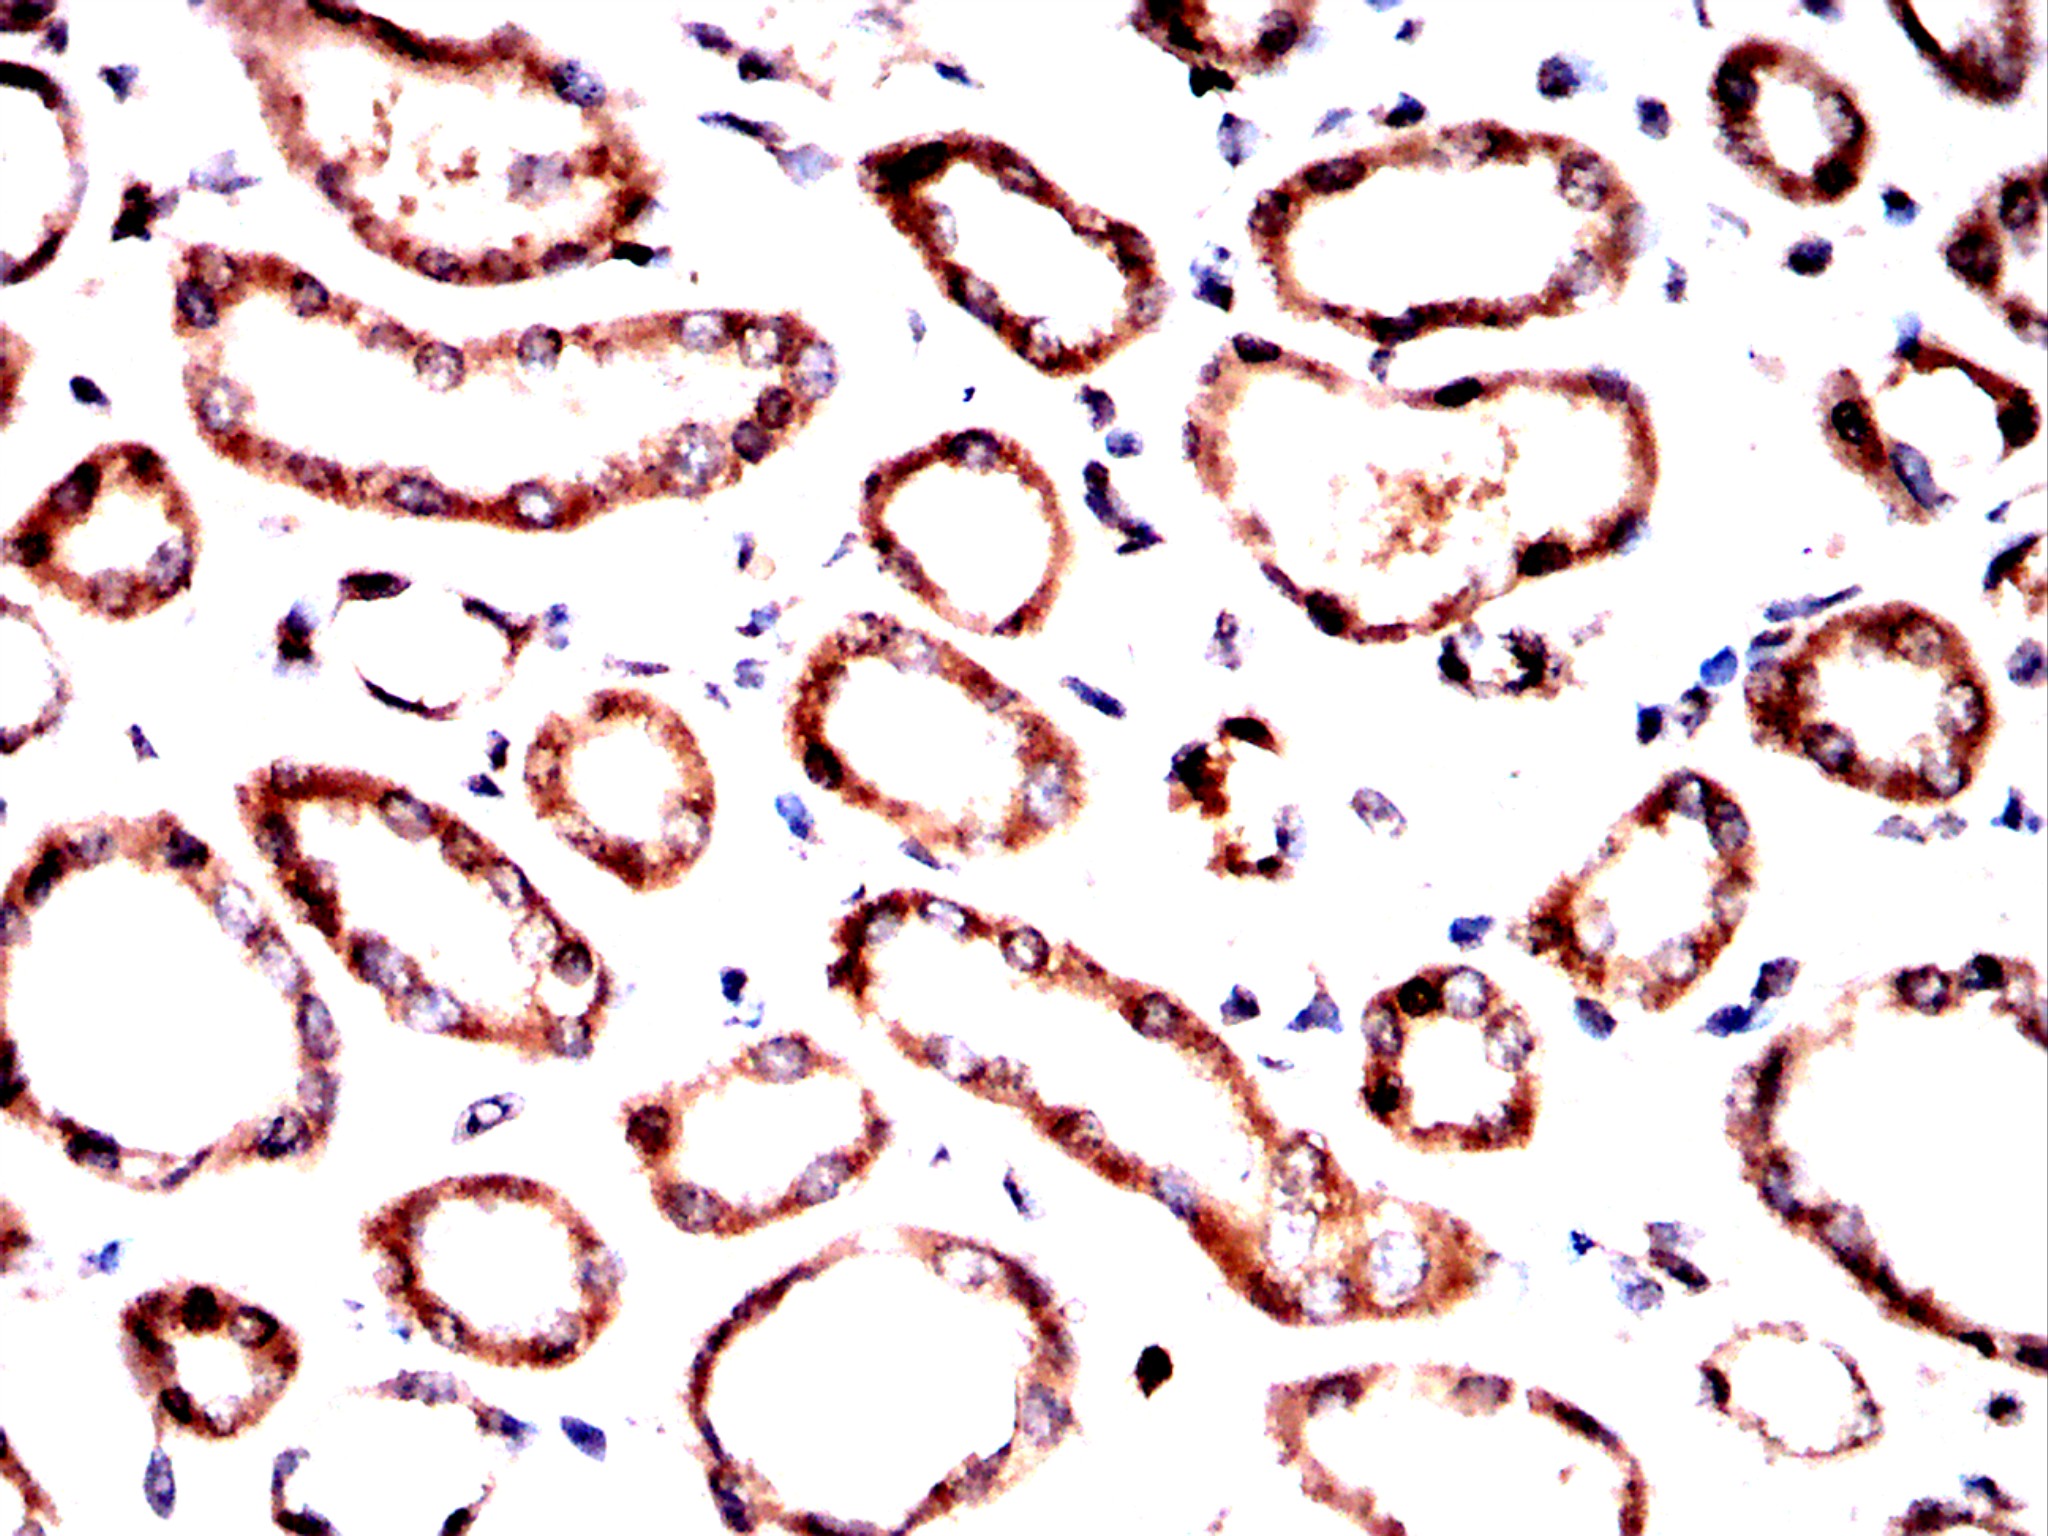

Immunohistochemical analysis of paraffin-embedded Kidney tissues using Pelo antibody with DAB staining. Pre-treat the sections with heat-mediated antigen retrieval using sodium citrate buffer (pH 6.0) (OM750020) for 2 minutes. Wash the sections with ddH₂O and PBS (OM750003). Block the tissue with 10% non-immune goat serum(OM760028) at room temperature for 30 minutes. Incubate the tissue with the primary antibody diluted at a ratio of 1:1500 at 4°C overnight. At room temperature, dilute the secondary antibody, Goat Anti-Rabbit IgG(H&L)-HRP (OM644332), at a ratio of 1:200 and incubate for one hour. Use DAB(OM760029)as the chromogenic agent. Counterstain the tissue with hematoxylin, and mount the tissue sections with neutral gum.IHC

Immunohistochemical analysis of paraffin-embedded Kidney tissues using Pelo antibody with DAB staining. Pre-treat the sections with heat-mediated antigen retrieval using sodium citrate buffer (pH 6.0) (OM750020) for 2 minutes. Wash the sections with ddH₂O and PBS (OM750003). Block the tissue with 10% non-immune goat serum(OM760028) at room temperature for 30 minutes. Incubate the tissue with the primary antibody diluted at a ratio of 1:1500 at 4°C overnight. At room temperature, dilute the secondary antibody, Goat Anti-Rabbit IgG(H&L)-HRP (OM644332), at a ratio of 1:200 and incubate for one hour. Use DAB(OM760029)as the chromogenic agent. Counterstain the tissue with hematoxylin, and mount the tissue sections with neutral gum.